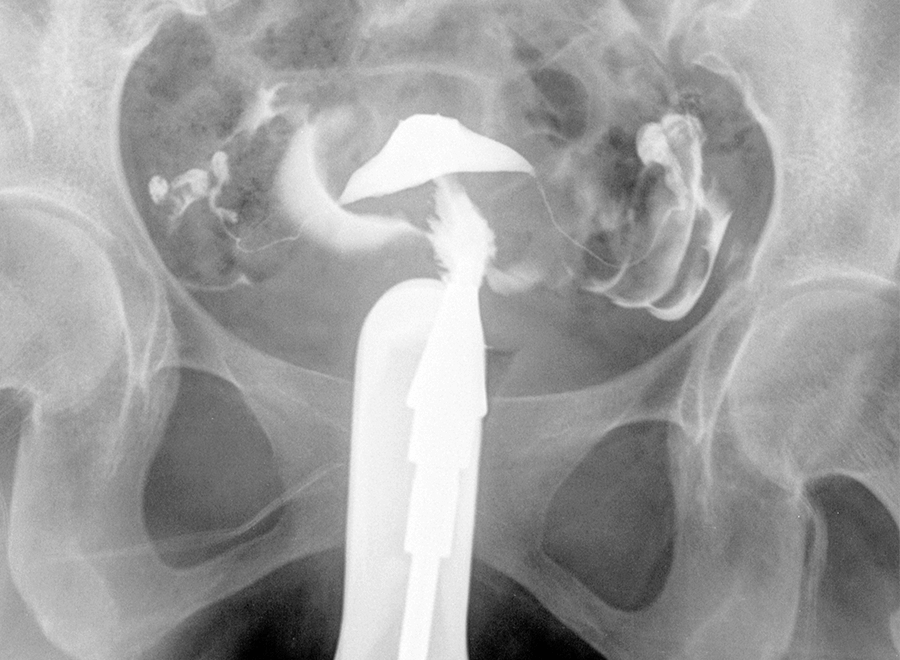

One hour prior to undergoing an HSG, it is often recommended to take an anti-inflammatory such as Ibuprofen, Motrin, or a similar over-the-counter nonsteroidal anti-inflammatory drug (NSAIDs). During the procedure, it is common to experience menstrual-like cramps or minor short-term discomfort. However, women with blocked fallopian tubes may experience more pain. Vaginal spotting is also fairly common following the procedure. The HSG involves no sedation or anesthesia, and most patients are capable of driving home or returning to work shortly after the procedure is over.